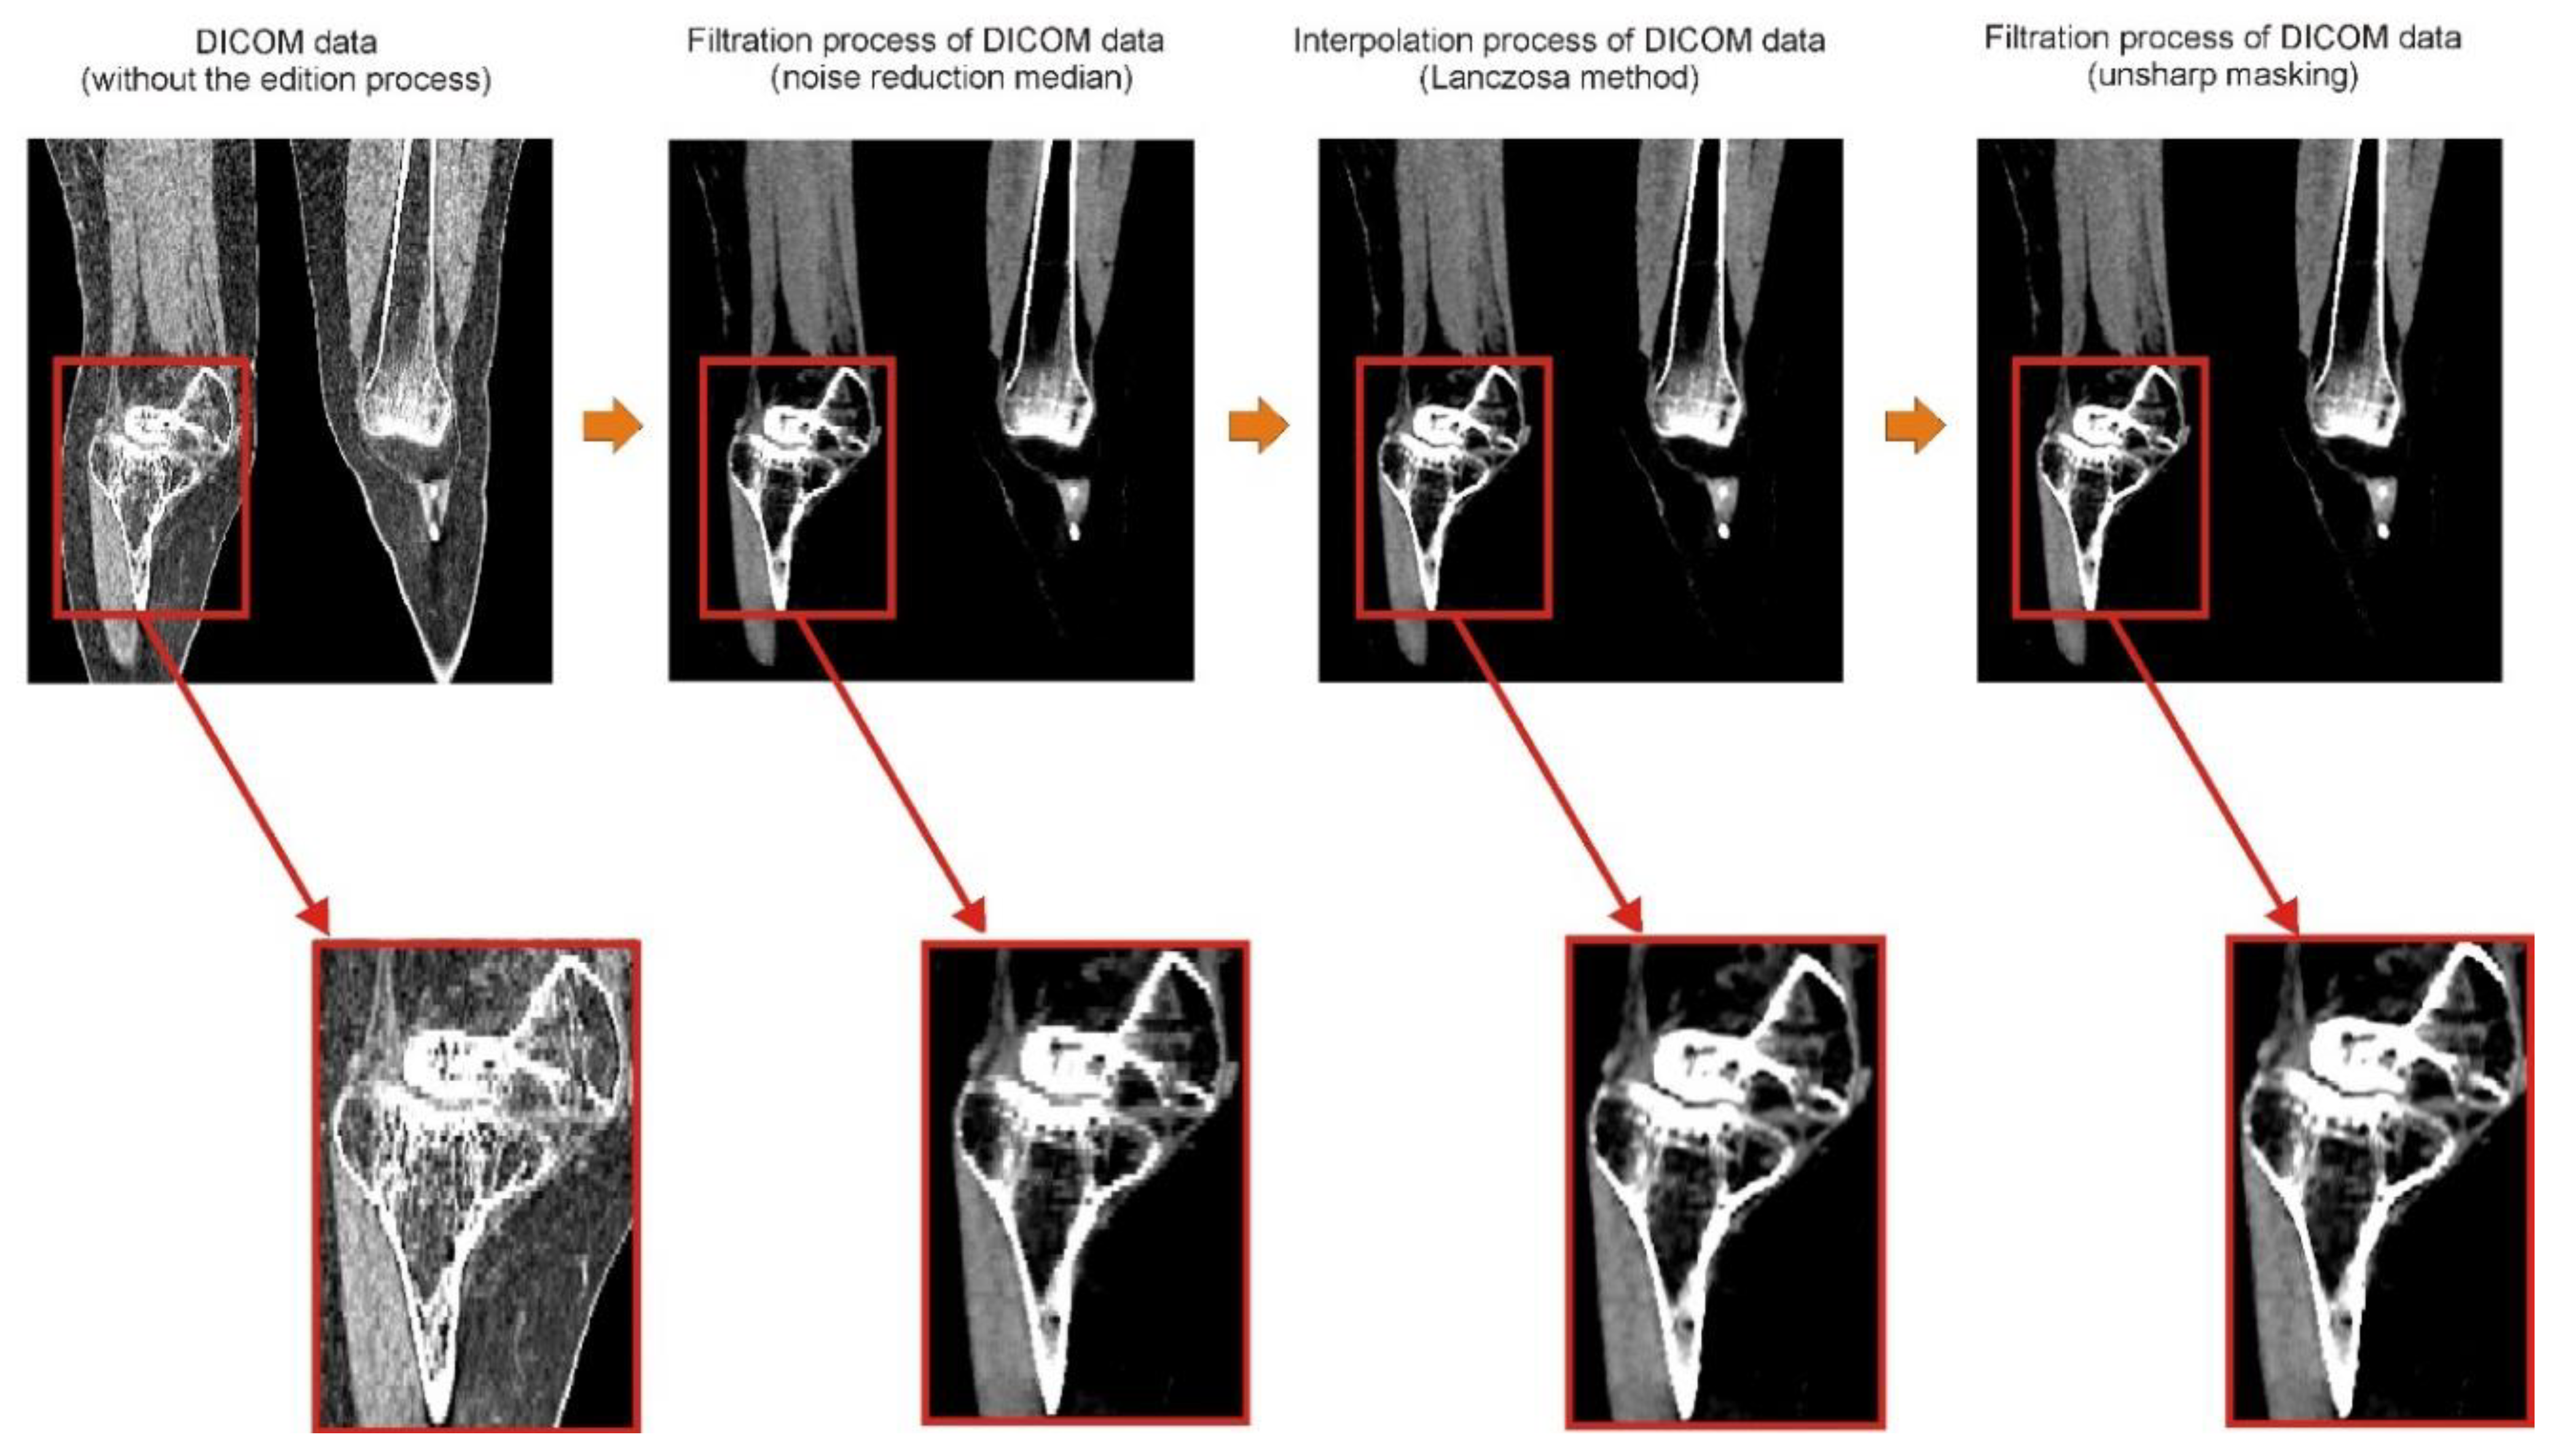

2.1. Digital Data Processing